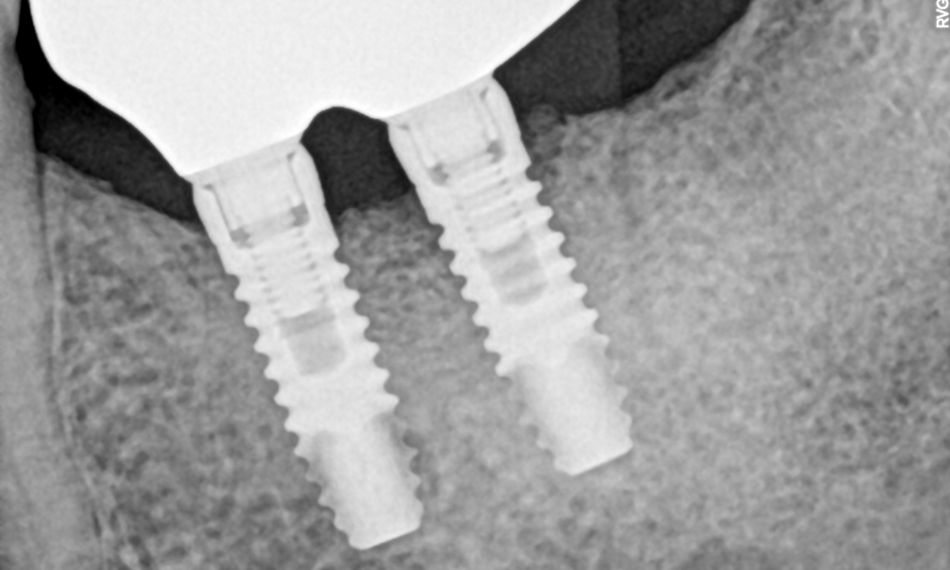

The following year, the clinical evaluation revealed similar findings, with the peri-implant soft tissues remaining healthy. The radiographic examination also showed that the peri-implant marginal bone levels were stable, with no evidence of bone resorption (Fig. 24).

Fig. 24

In 2023, similar results were observed, with the peri-implant tissues remaining healthy. The radiographic examination confirmed that marginal bone levels were intact. The treatment was successful, and the patient reported satisfaction with the esthetic and functional outcomes. (Figs. 25,26).

Fig. 25

Fig. 26